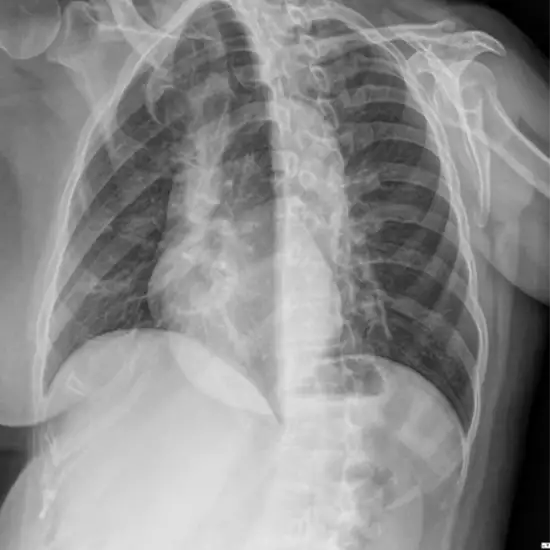

The X-Ray Lower Ribs on the Left: The AP test is a type of imaging that takes pictures of the lower ribs from the front to the back (9-12). It can find infections, tumors, broken ribs, the shape and size of the lower ribs, and blood vessels too narrow.